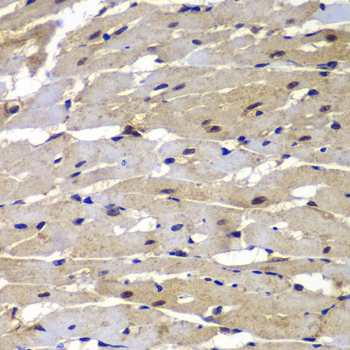

Immunohistochemistry of paraffin-embedded rat heart using PSMB8 at dilution of 1:100 (40x lens).